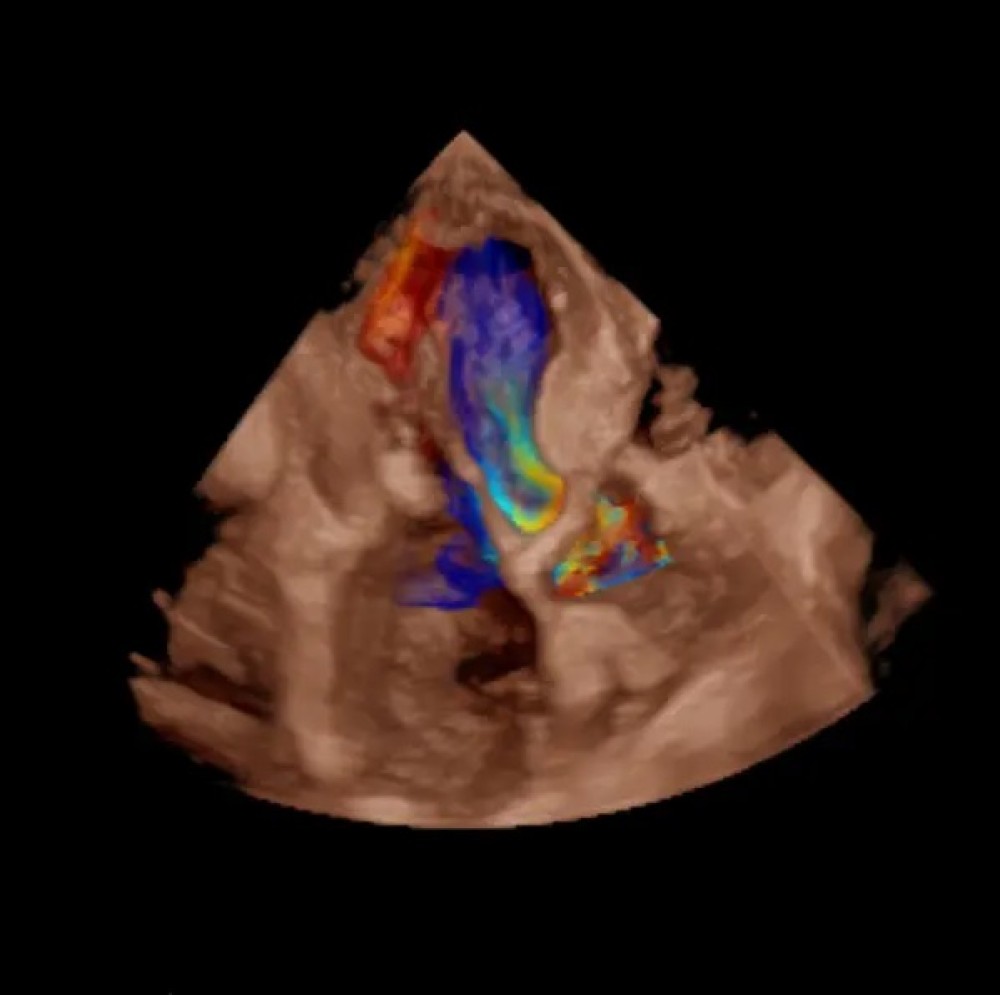

GE Vivid S70N Dimension — mütəxəssis kardiologiyası üçün nəzərdə tutulmuş inkişaf etmiş ultrasəs sistemi. Bu model təkmilləşdirilmiş 4D ekokardioqrafiya funksiyalarına malikdir və matriks  (TEE) problarını dəstəkləyir. Sistem həmçinin kvantitativ həcmli məlumatların təhlili və qiymətləndirilməsi üçün geniş alətlər toplusunu təmin edir.

cSound platforması əsasında işləyən Vivid S70N Dimension ürək və damar strukturlarının yüksək dəqiqlikli görüntülənməsini təmin edir, beləliklə kardiologiya üzrə mütəxəssis mərkəzlər, funksional diaqnostika şöbələri və yüksək diaqnostik dəqiqlik tələb edən tibb müəssisələri üçün ideal seçimdir.